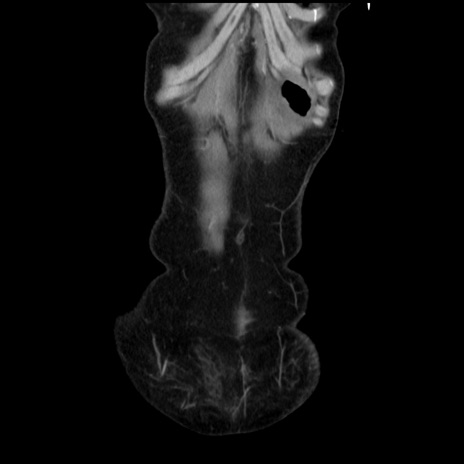

症例32(冠状断像)

矢状断像